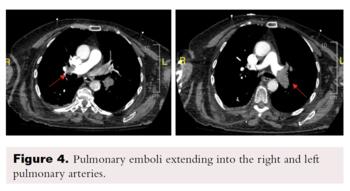

Transthoracic echocardiography showed severe dilated right chambers. There was a large, highly mobile right atrial thrombus (Figure 2), with severe systolic right ventricular dysfunction: severe tricuspid regurgitation and pulmonary artery systolic pressure of 100 mmHg (Figure 3).